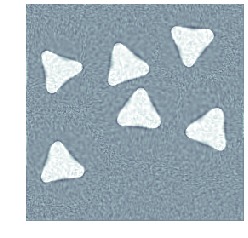

5.3 Consistent topology and inconsistent intensities

Here, topology of the template is consistent with that of the target, but intensities differ. The template, which is shown in fig. 2(a), is registered against tomographic data shown in fig. 2(c). The (unknown) target used to generate data is shown in fig. 2(b). Also, data has a noise level corresponding to a \acPSNR of and kernel size is , which should be compared to the size of the image domain . The final reconstruction is shown in fig. 2(h), which is to be compared against the target in fig. 2(b). Figure 2 also shows image, deformation and template trajectories.

We clearly see that metamorphosis based indirect registration can handle a template with wrong intensities. As a comparison, see fig. 1(c) for the corresponding \acLDDMM based indirect registration using the same template and data. Furthermore, the different trajectories also provides easy visual interpretation of the influence of geometric and intensity deformations.